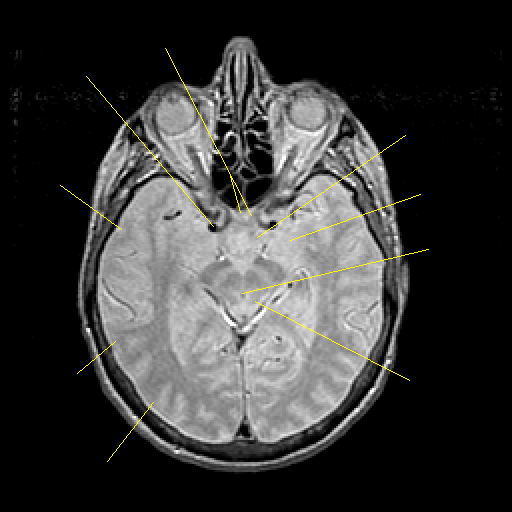

Proton density-weighted structural MR: Slice 23

Slice 23

Pointers

Labeled